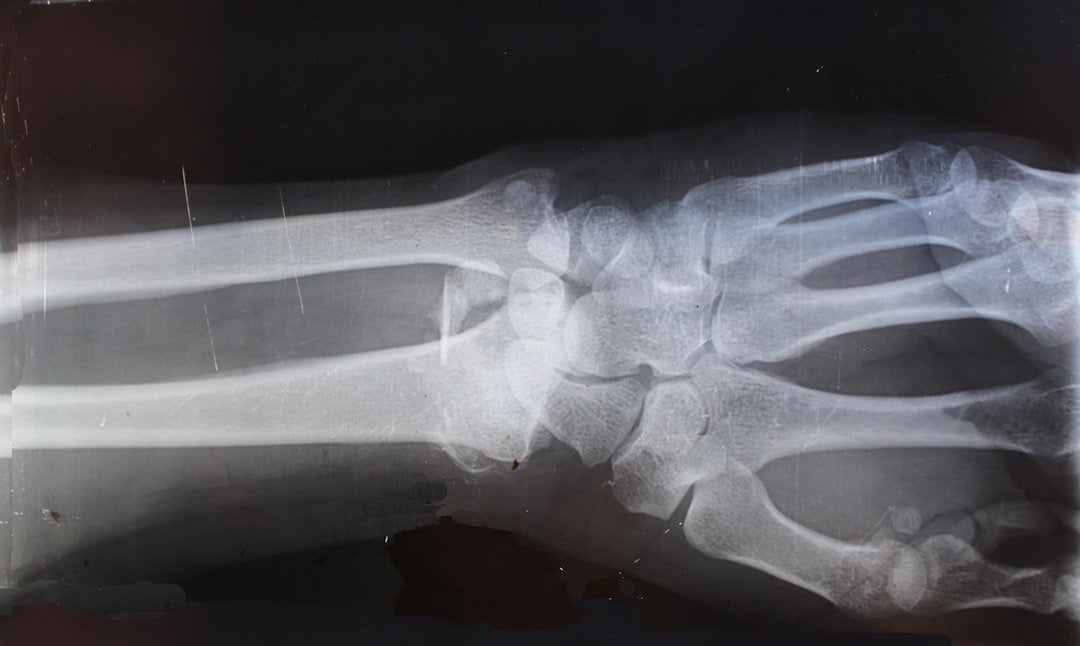

이제 정형외과에서 어떤 치료와 진료를 받을 수 있는지를 알아보도록 하겠습니다. 경기도 이천시 일요일 정형외과는 다양한 부상 및 질환에 대한 치료를 제공하고 있으며, 일반적인 외상 치료뿐만 아니라, 만성 통증 관리, 관절염, 골절 치료 등도 포함됩니다. 이러한 다양한 서비스는 여러분이 건강을 회복할 수 있도록 돕기 위해 존재합니다.

또한, 정형외과의사는 여러분의 상태를 빠르게 파악하고 적절한 치료법을 제시해 줄 것입니다. 예를 들어, 운동 중 발생한 염좌나 골절은 신속한 진단과 치료가 필요합니다. 치료가 늦어짐에 따라 통증이 심해질 수 있으니 조기에 진료를 받는 것이 중요합니다. 경기도 이천시 일요일 정형외과 주말 진료 시간에 방문하여 전문의와 상담해 보면 좋을 것 같습니다.